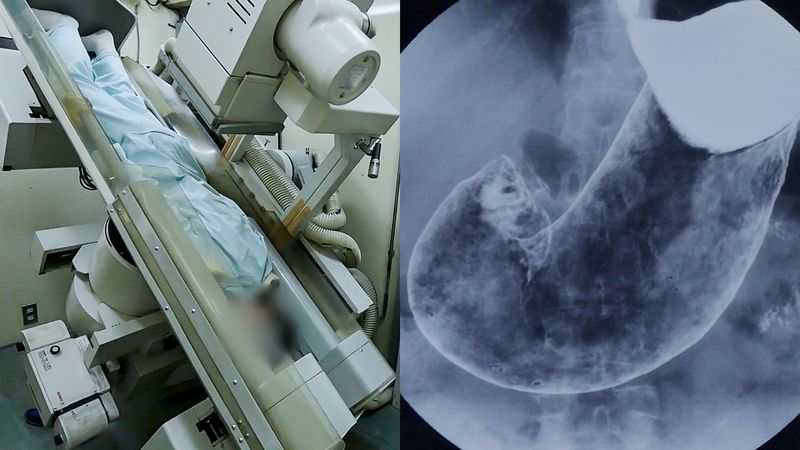

国が推奨している胃がん検診のうち、主流なのがバリウムX線検査だ。しかし、この検査には隠されたリスクが多いという。ジャーナリスト・岩澤倫彦さんの著書『がん「エセ医療」の罠』(文春新書)より、バリウム検査を受けて九死に一生を得た61歳男性のエピソードを紹介する――。

・胃がん検診:X線検査、または内視鏡検査(胃カメラ)